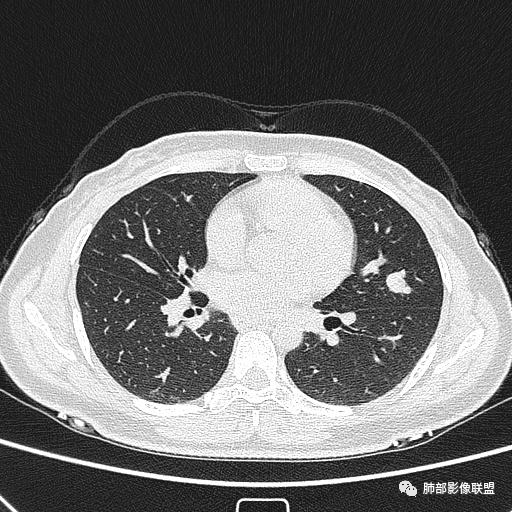

1、临床特点:30岁女性,体检发现肺部结节。

2、影像特点:左肺上叶舌段实性密度结节,边界清楚,略呈不规则三角形,边缘多平直,未见分叶、毛刺及明显收缩。密度均匀,未见钙化、脂肪密度或低密度液化空洞,持续渐进强化。未显示相关支气管及血管出入、血管贴边等。未见明确卫星病灶。双肺门及纵隔未见增大淋巴结。

3、病例小结:年轻女性,体检发现,左肺上叶舌段实性结节,边缘清楚光滑,未见分叶毛刺及收缩,亦未见边界清晰的磨玻璃晕,与支气管血管了无瓜葛等,较为符合的是肺良性结节。

CT:形态:圆形或椭圆形结节,边界清楚,无分叶及毛刺、无胸膜凹陷征及血管集中等恶性征象,无卫星病灶,周围无纹理增多及粘连等;大小:平均直径3cm,从<1cm到>10cm均有报道;密度:均匀、软组织密度,偶有出血、囊变、钙化;强化方式:多为均匀明显强化,少数不均匀强化;其它特殊征象:血管贴边征 、空气半月征 、晕征,偶见纵隔淋巴结肿大。